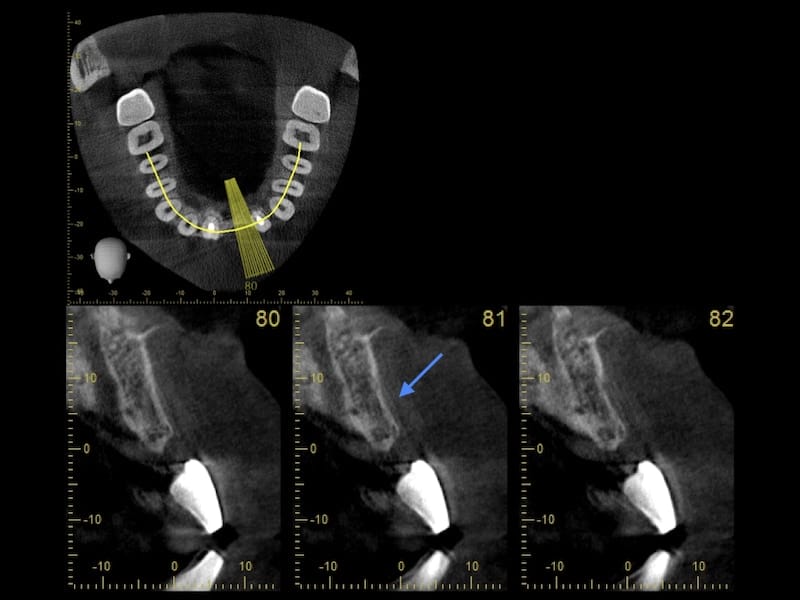

我們先治療控制牙周狀況後,開始進入利用數位電腦斷層掃描的方式,先評估他預計植牙缺牙區,齒槽骨的條件。

從電腦斷層的影像顯示,在預計要植牙的位置,齒槽骨有萎縮現象,骨頭寬度條件不足。我的治療植牙手術相關計畫是分為兩階段。第一是要先以俗稱補骨的『引導骨再生手術』,增加骨量。等待約半年的時間,在進入到第二階段,植入人工牙根。

植牙補骨前電腦斷層檢查,箭頭處顯示骨頭寬度不足